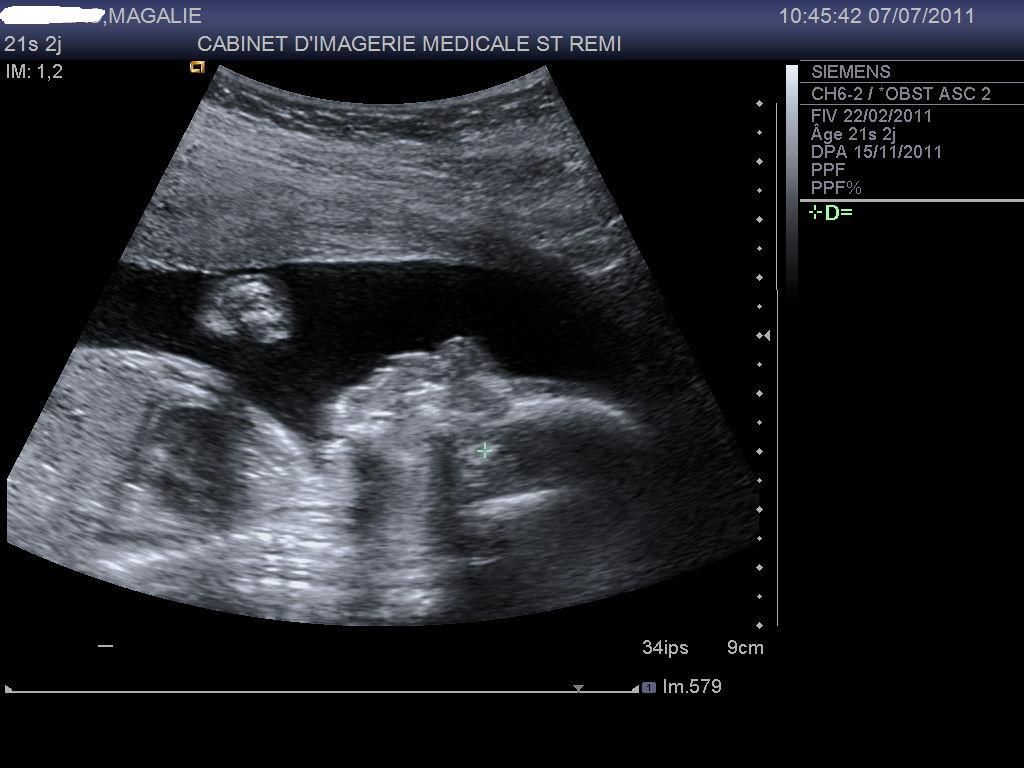

Par malaka4 : le 17/07/11 à 19:43:30

| Dire merci | Un petit coucou à toutes !! Je prend régulièrement de vos nouvelles même si je ne participe pas bcp, je suis vos aventures J'ai enfin récupéré les images de mon écho du 07/07 du 2ème trimestre, alors j'ai le plaisir de vous présenter ma petite NAÏS ![]() |